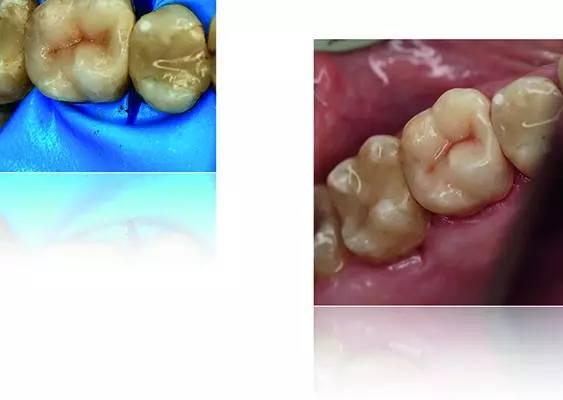

W tym wydaniu m.in: koferdam w adhezyjnych protokołach rekonstrukcyjnych, Low Dose – przełom w tomografii komputerowej CBCT, odpowiedzialność karna lekarza za błąd medyczny, wykorzystanie sonoabrazji w różnych dziedzinach stomatologii.